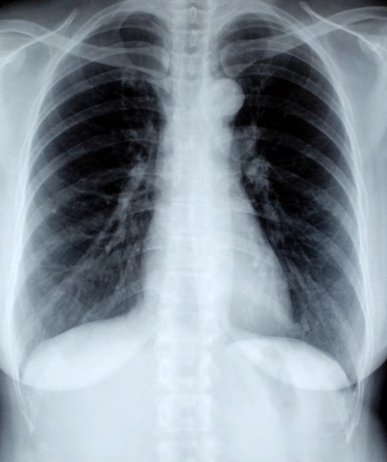

💉 필수 폐 검사 항목

- 흉부 X-ray: 폐렴, 폐암, 결핵 등 확인

- 폐기능 검사 (PFT): 폐활량, 산소교환 능력 체크

- CT 검사: 미세 병변까지 정밀 진단 가능

- 종합건강검진 시 포함되는 경우 많음